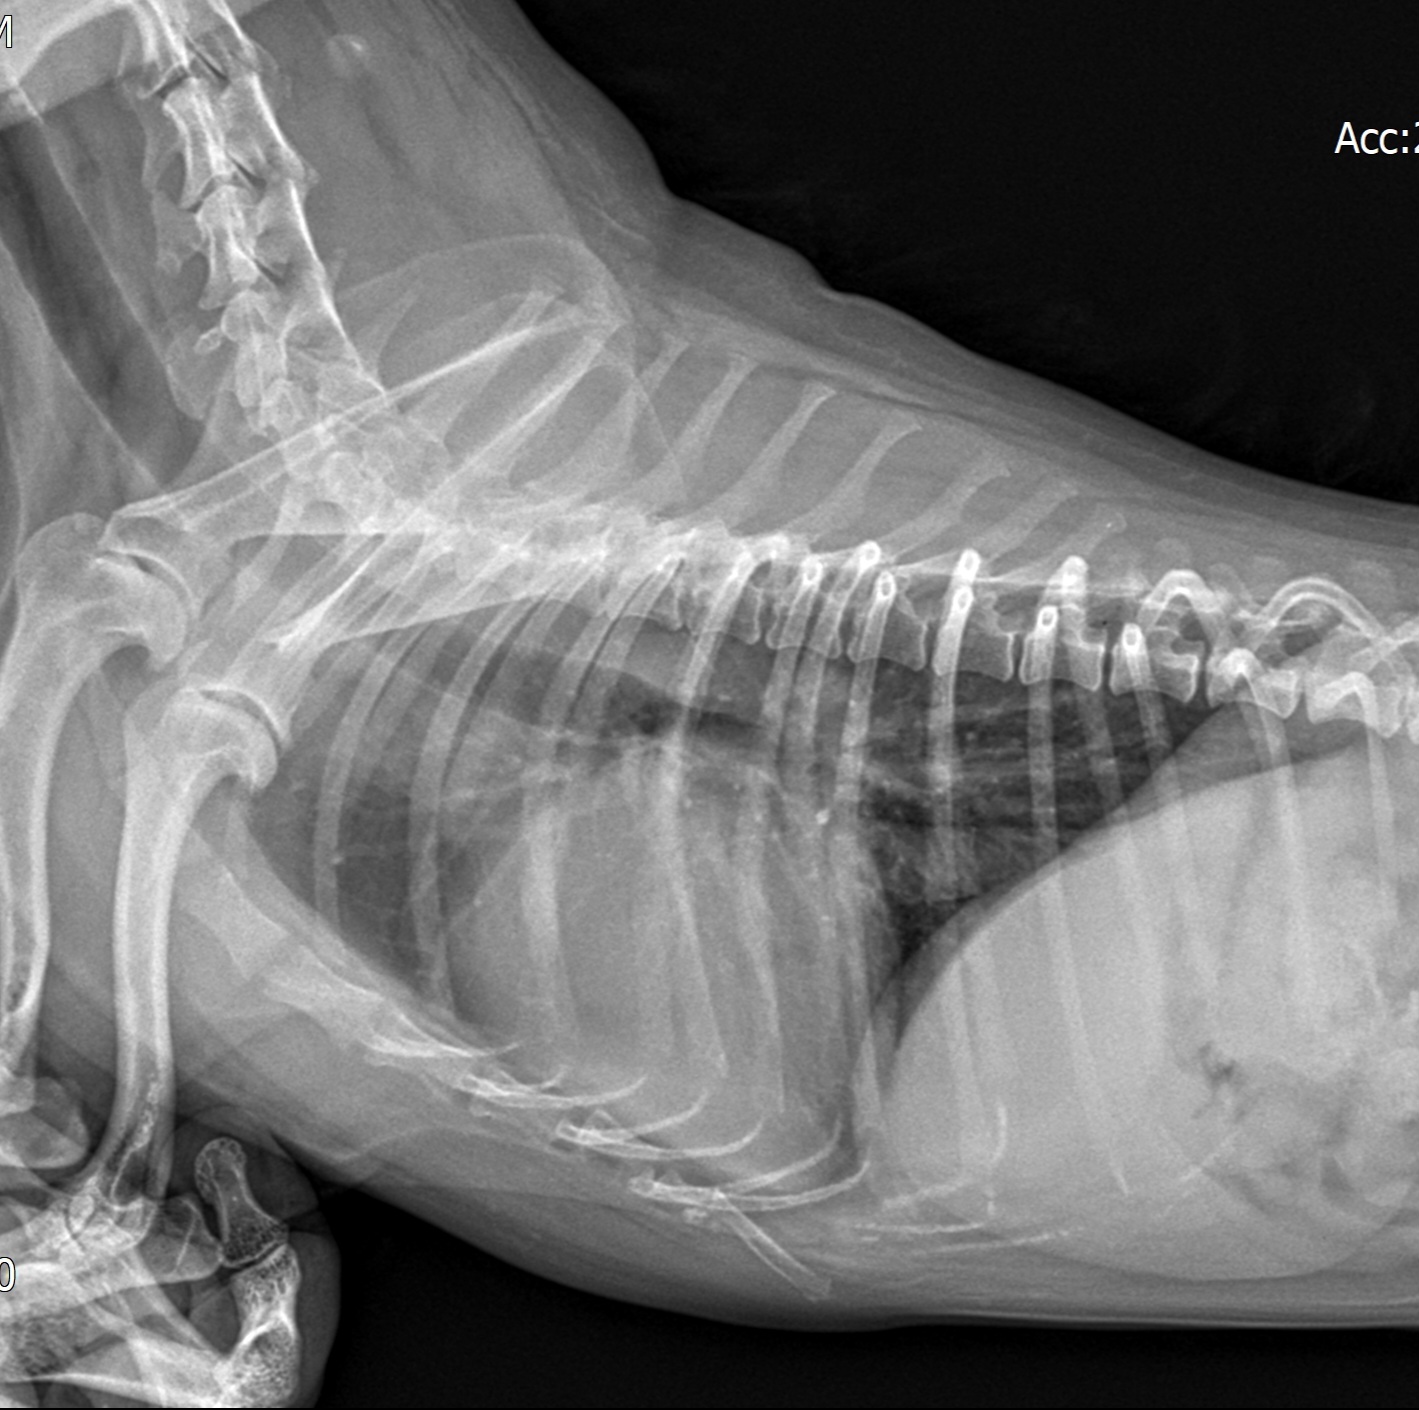

심장병 진단 방법

- 흉부 X-ray: 심장 크기, 폐 상태 확인

※ 정확한 진단은 심장 전문 수의사의 초음파 검사가 필수입니다.